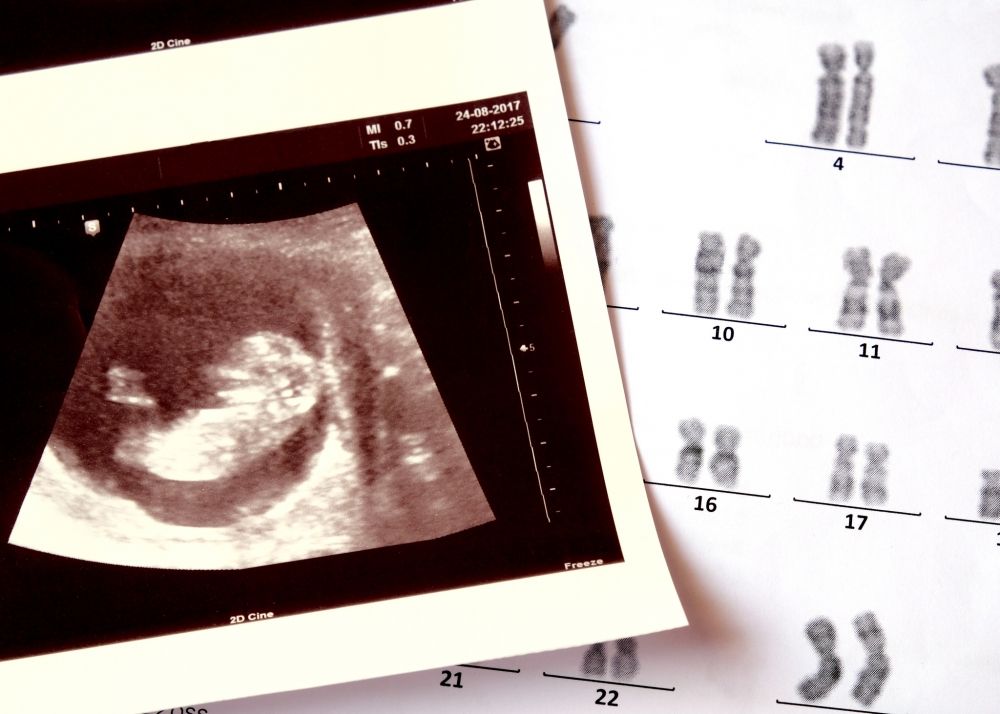

對很多新手父母來說,可能搞不清楚「結構性超聲波檢查」跟平時產檢的超聲波檢查有何分別?分別在於後者主要看看胎兒的心跳、大小、胎位、羊水量和胎盤位置,所需時間較短;而前者則詳盡許多,醫生會檢查胎兒的頭部、腦部、五官、內臟器官、脊椎、四肢、臍帶、性器官等結構是否異常,可檢查出常見的先天性缺陷,如唐氏、唇裂、先天性心臟病、腦部結構異常、四肢結構異常、 脊柱問題、染色體異常、神經管缺陷等。

醫生會利用二維黑白或三、四維彩超影像技術,觀測肚內胎兒的發育情況。若檢測結果顯示胎兒發育結構異常,可給予父母心理準備,亦可提早諮詢及安排胎兒出生後的後續治療與照護。若情況嚴重,父母可選擇終止懷孕。政府規定懷孕24週後禁止終止懷孕(除非為挽救孕婦生命),因此爸爸媽媽記得要在合適時間預約接受結構性超聲波檢查。